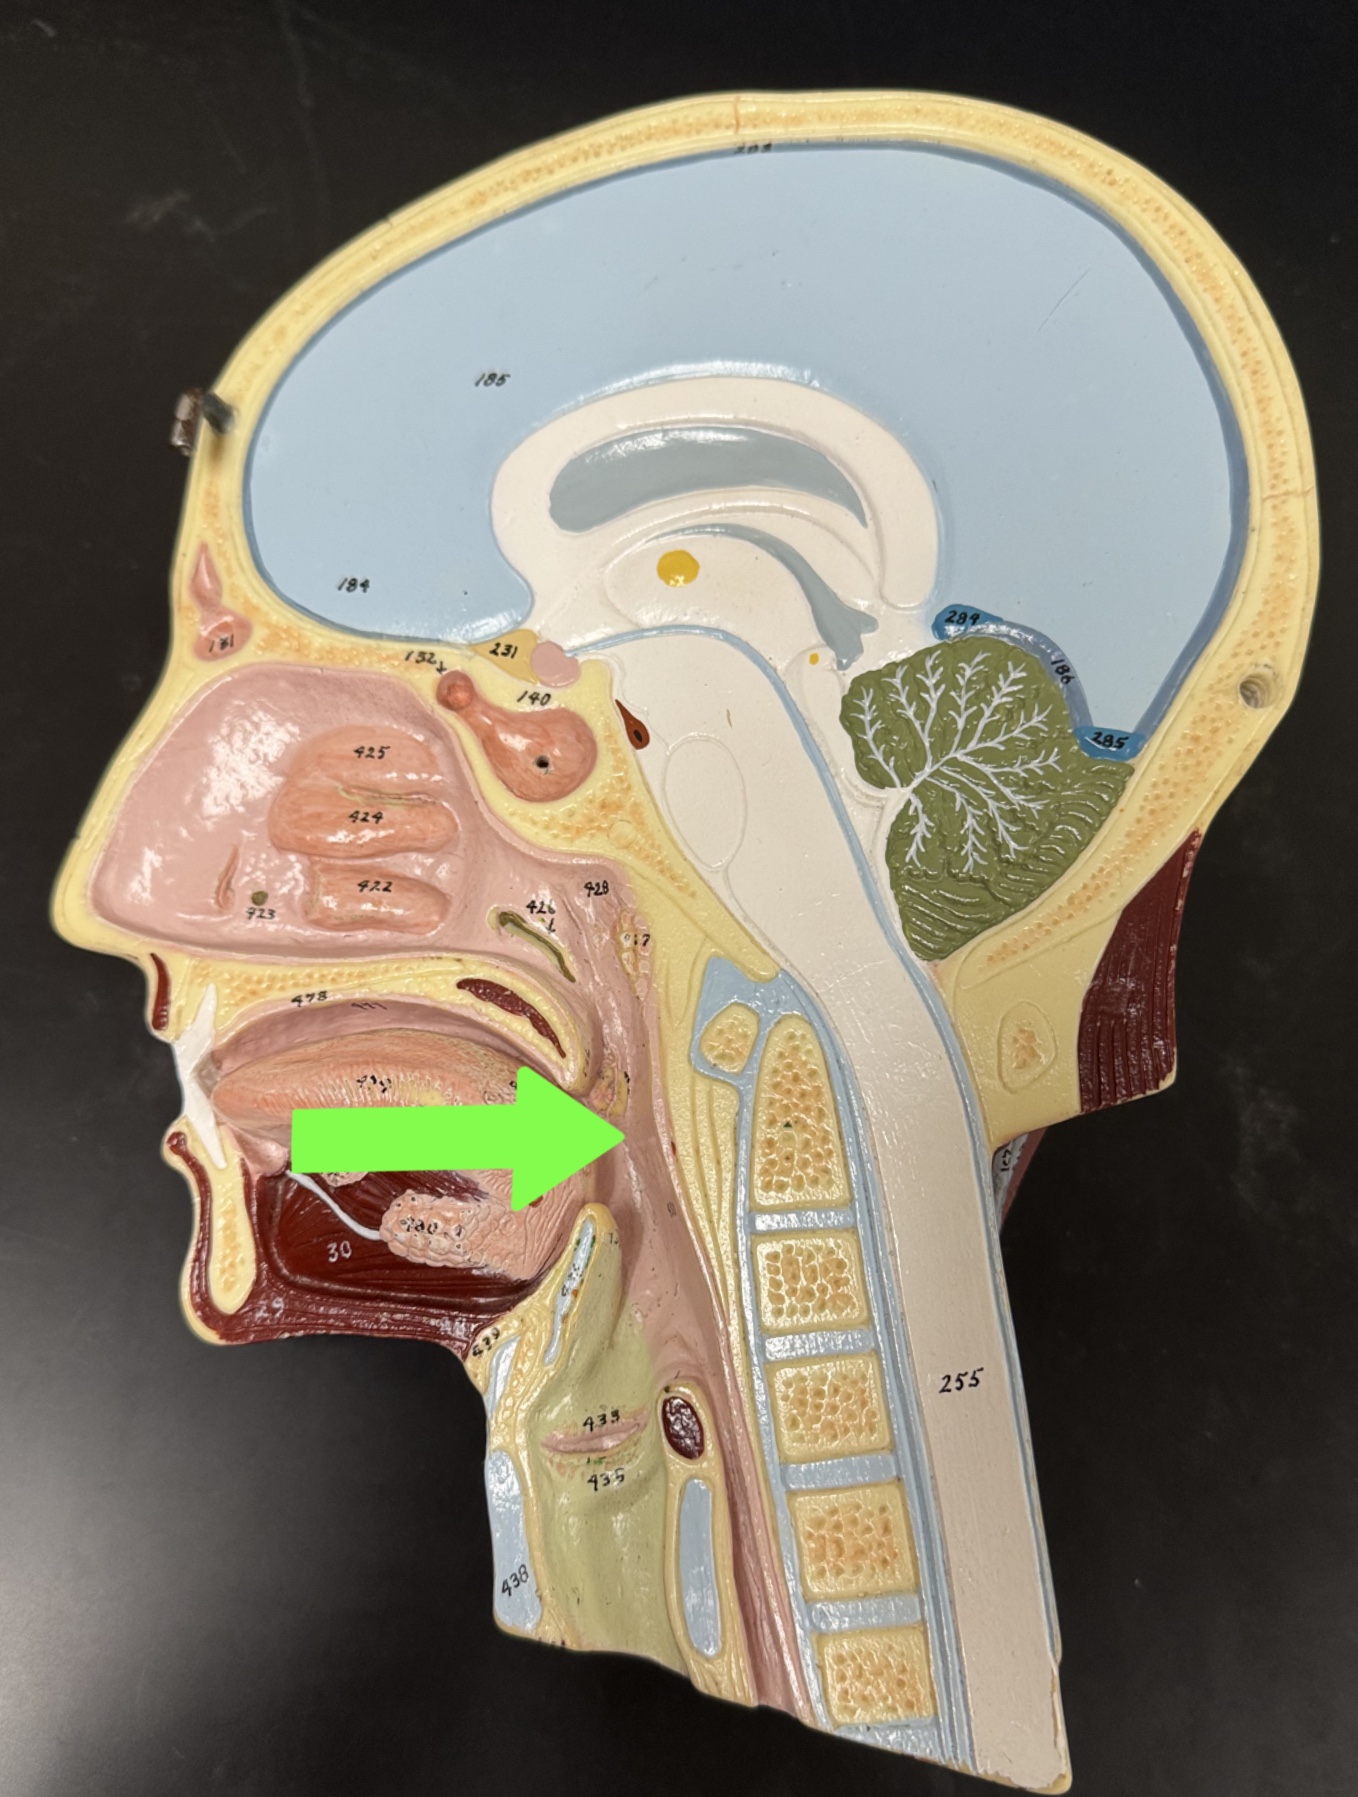

Half head

Oral cavity: tongue

Tongue

Salivary glands

Esophagus

Epiglottis

Pharynx